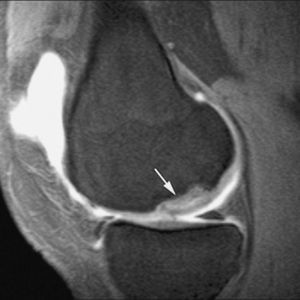

El choque posterior se refiere a un grupo de procesos patológicos resultado de traumatismos por flexión plantar forzada del pie. El mecanismo lesional se ha comparado al de un cascanueces ya que la vertiente posterior del astrágalo y los tejidos blandos adyacentes son comprimidos entre la tibia y el calcáneo durante la flexión plantar del pie. Este síndrome se ha descrito en bailarinas de ballet clásico pero también se describe con frecuencia en deportistas. Las causas más frecuentes son óseas: os trigonum (osículo accesorio del tubérculo postero-lateral del astrágalo que puede persistir sin fusionarse en la vida adulta en un 7% de los individuos), un tubérculo postero-lateral del astrágalo elongado denominado proceso de Stieda, una inclinación inferior en margen posterior de techo tibial (tercer maléolo), la prominencia del proceso posterior del calcáneo y los cuerpos libres. Lesiones de partes blandas que condicionan choque son la sinovitis del flexor largo del primer dedo, los recesos sinoviales posteriores de las articulaciones subastragalina posterior y tibio-astragalina y el ligamento intermaleolar posterior. La RM es útil para establecer el diagnóstico de choque posterior. La presencia combinada de edema óseo y sinovitis en los recesos capsulares posteriores sugieren la existencia de este síndrome. El ligamento intermaleolar posterior es una variante anatómica presente en aproximadamente un 19% de los pacientes. En ocasiones, este ligamento puede engrosarse por traumatismos o fricción mecánica repetida. La RMA permite identificar este ligamento y las alteraciones del mismo que pueden condicionar un síndrome de choque posterior, como engrosamiento y sinovitis focal19,23.